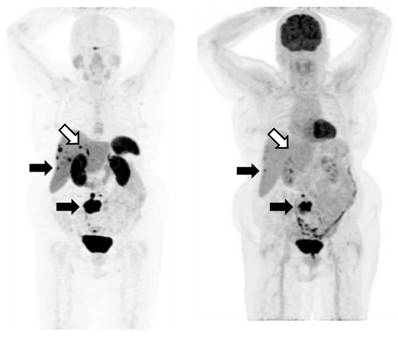

Figure 3

An example of an SSTRI ([68Ga]-DOTATATE) and FDG scan pair. The MIP (maximum intensity projections) images from the respective PET data sets are shown. The subject has SSTRI-dominant disease which exhibits some lesions with spatially concordant FDG uptake (closed arrows). While there are some sites of disease which are SSTRI-positive but FDG-negative (open arrows), importantly, there are no sites which are FDG-positive and SSTRI-negative. The example shown demonstrates a NETPET score of P3a, indicating that (i) the scans are positive on both SSTRI and FDG, and (ii) there were up to 2 lesions demonstrating approximately equivalent uptake between SSTRI and FDG, with the remaining lesions demonstrating greater SSTRI avidity than FDG.